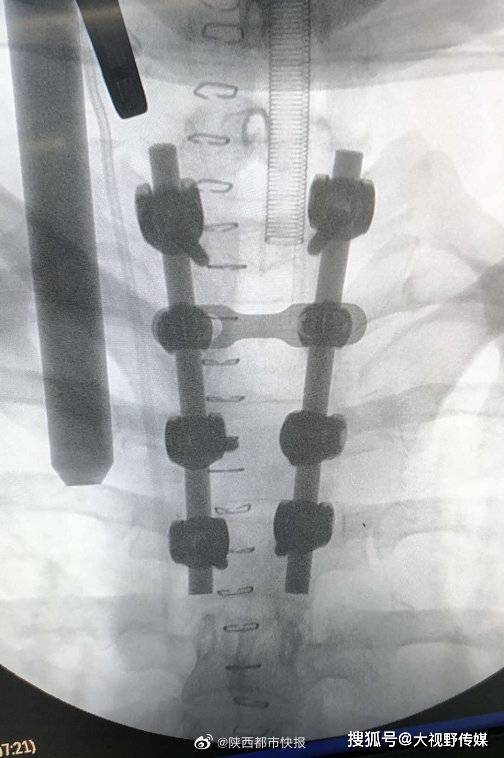

翌日凌晨2点多,患者进入手术室,医生打开椎管看到了暗红色的血凝块,将血凝块取出,仔细观察脊髓慢慢恢复了搏动,然后对椎体进行了钉棒内固定及椎旁植骨融合手术。当天下午3点钟再次查看了病人,患者双下肢肌力已经恢复到4级,基本正常,双侧髋以下活动机能正在逐步恢复中。(记者:赵杨梅子)